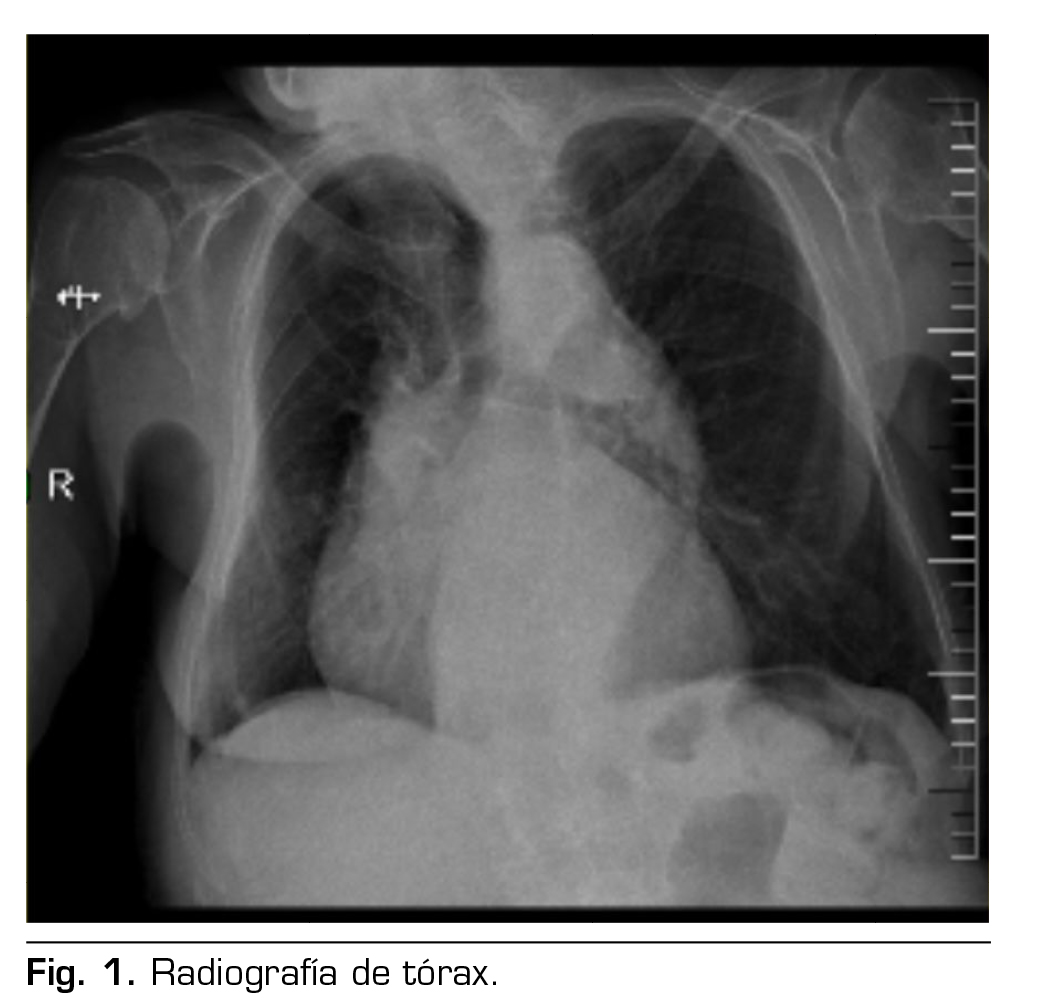

Por lo anterior, se define como técnica anestésica y analgésica bloqueo II/IH bajo guía ecográfica. Posicionamos a la paciente en decúbito supino, previa monitorización ASA básica, se realiza asepsia en zona de punción, se usó una sonda lineal estéril de alta frecuencia, se ubicó entre la cresta iliaca anterosupeior y la cicatriz umbilical, orientándolo un poco más cefálico de lo habitual; en esta posición se logra visualizar los nervios ilioinguinal e iliohipogástrico entre el músculo transverso del abdomen y el músculo oblicuo interno como se muestra en la Figura 2. Después de la visualización, se utilizó una aguja 22 G de 50 mm abordaje en plano; previa aspiración se inyectó ropivacaína a una concentración de 0,75 % con un volumen aproximado de 10 ml. Posteriormente procedimos a realizar sedación con propofol 2 mg/kg/h, se mantuvo en puntuación de 3 en la escala de Ramsay, sin cambios hemodinámicos de importancia, además se administró dexametasona a dosis de 4 mg en el intraoperatorio y coadyuvantes analgésicos como paracetamol y metamizol. Tras la hernioplastia de abordaje abierto con tiempo quirúrgico de 35 min, sin complicaciones o incidencias, se la traslada al área de recuperación postoperatoria según protocolo, con evaluación de puntuación de dolor mediante escala visual analógica 2 de 10. Hemodinámicamente estable y con dolor controlado, cumple criterios de alta médica; se usó el sistema de puntuación postanestésico para determinar si la paciente está preparada para ir a casa, obteniendo un puntaje de 9 según el protocolo del hospital; se deja pautada analgesia de rescate para domicilio con paracetamol y antinflamatorios condicionados según dolor.